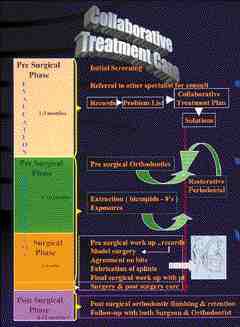

ABSTRACT: In 1994, the Dental Clinic was created at the Queensway Carleton Hospital (QCH), through the generous donation of Dr. M Lorne E. Macalchlan , a long-term care patient. The fund was earmarked for use in regards to elderly patients at the institution. The hospital itself is a 201-bed facility located in Nepean, Ontario, Canada … Read more